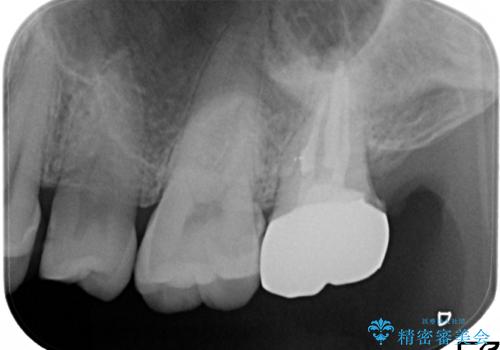

奥歯が感染をおこし強い痛みを出してしまっていたため、顕微鏡を用いた根管治療をおこない根管内を洗浄した後かぶせ物を製作しました。

ひとつひとつの治療を丁寧に行うことで今後も長く使う事ができます。